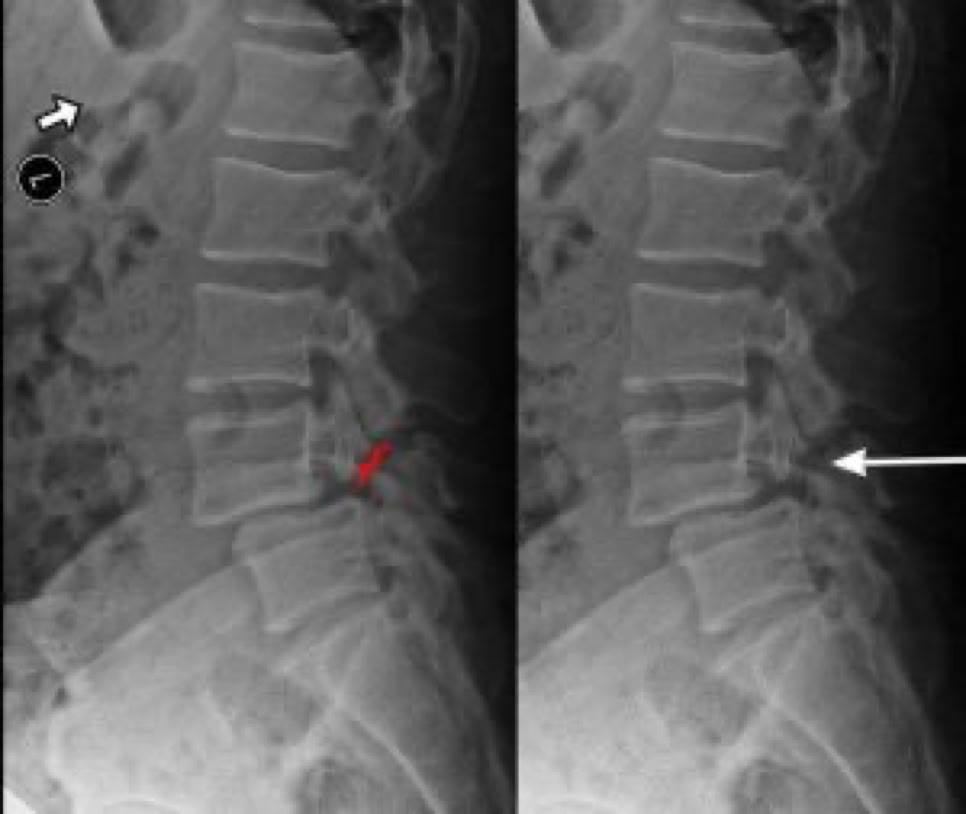

Spondylolisthesis is most commonly observed in the lumbar spine, which bears the majority of the body’s weight. To evaluate spinal instability, X-rays are typically taken while the patient bends forward (flexion) and backward (extension). Under normal conditions, there should be no significant motion at the affected level. However, increased movement between the flexion and extension X-rays often correlates with more pronounced symptoms, indicating a greater degree of instability and discomfort for the patient.

fracture of the pars defect

anterior slippage of vertebra

X-RAY SHOWING A PARS FRACTURE DEFECT

THE WHITE OUTLINE SHOWS THE SLIPPAGE.